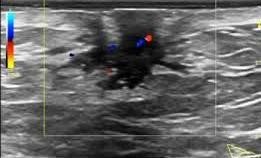

сложная киста молочной железы.